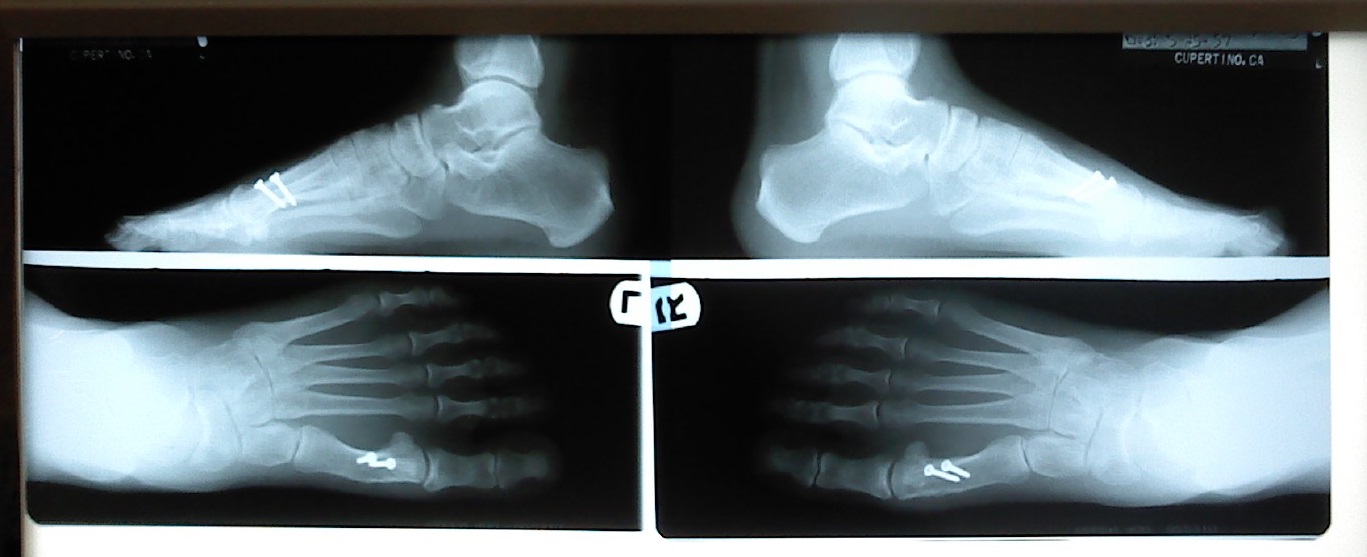

これ。このネジが13年以上私の両足に入っていたんですね。

13年間も入っていたわりに、新品みたい。そりゃ、体の中なんだから、錆びないような材質をつかってるんでしょうけど、こんなに大きい、本当にネジの形をしているもの使うのねーっと、改めて感心しました。これが証拠のX-Ray写真。

13年前、外反母趾の手術をして、ネジはそのまま体内放置されていました。多分、ダンスをしていなければ、そのまま一生ネジ付きで死んでいったのかもしれません。でも、3ヶ月ぐらい前から右足の付け根が痛み出したので、さっそく医者に見せました。ネジが神経にぶつかってるから痛いんでしょうとのこと。で、ドイツ出張の直後に手術の予定を組んだという次第です。ちなみに、今ではこんなに大きなネジは使わないとの事でした。